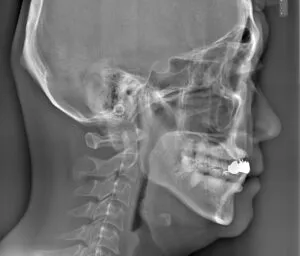

セファロレントゲン:矯正専門の側面X線で顎の位置を分析